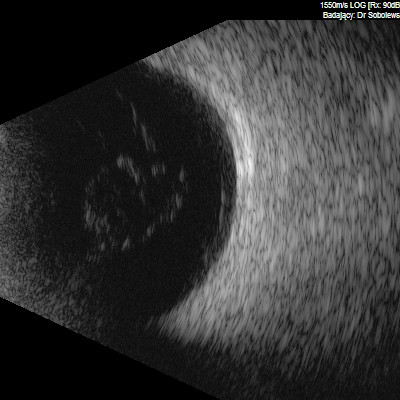

Przedstawiane obrazy ultrasonograficzne® są oryginalne i pochodzą z mojej praktyki lekarskiej